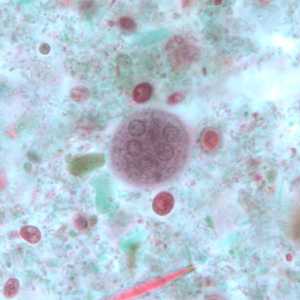

E. coli cysts stained with trichrome.

Figure A: Immature cyst of E. coli, stained with trichrome. Notice the presence of only two nuclei, and a large glycogen vacuole.

Figure B: Mature cyst of E. coli, stained with trichrome. Five nuclei are visible in this focal plane.

Figure C: Mature cyst of E. coli, stained with trichrome. In this specimen, at least five nuclei are visible in the shown focal plane.

Figure D: Mature cyst of E. coli, stained with trichrome. In this specimen, at least five nuclei are visible in the shown focal plane.

Figure E: Mature cyst of E. coli, stained with trichrome. This figure and Figure F represent the same cyst shown in two different focal planes. Eight nuclei can be seen between the two focal planes. Also, above the cyst in this figure, a trophozoite of Endolimax nana can be seen.

Figure F: Mature cyst of E. coli, stained with trichrome. This figure and Figure E represent the same cyst shown in two different focal planes. Eight nuclei can be seen between the two focal planes.